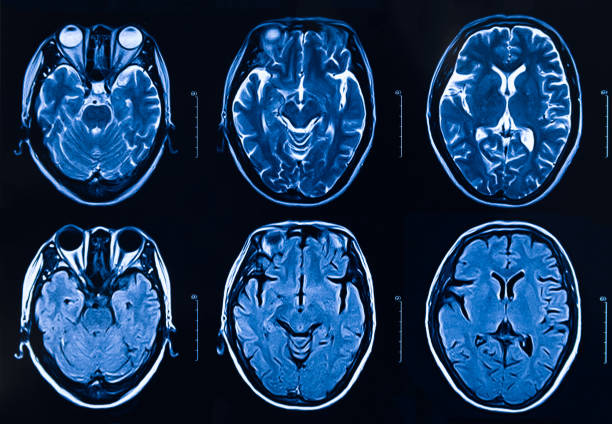

資格標準包括非外傷性幕上血腫小于60mL和格拉斯哥昏迷評分大于5。所有患者均在神經(jīng)科學(xué)重癥監護病房接受監測,以了解間充質(zhì)干細胞/基質(zhì)細胞輸注的安全性和耐受性以及不良事件。我們還探索了使用細胞因子作為生物標志物來(lái)評估對細胞療法的反應。我們篩選了140名患者,將符合資格標準的9名患者分為三個(gè)劑量組:50萬(wàn)個(gè)細胞/kg、100萬(wàn)個(gè)細胞/kg和200萬(wàn)個(gè)細胞/kg。補充圖1和補充表1中列出了報告試驗綜合標準圖和詳細的資格標準。

本研究納入2018年1月1日至2020年10月31日發(fā)病168小時(shí)內發(fā)生急性ICH的患者。間充質(zhì)干細胞被靜脈注射給9名患者(5名女性,4名男性),平均年齡(范圍)為61(36-84)歲。表1總結了人口統計學(xué)和臨床??特征 。出于描述目的,患者按照入組順序獲得編號,并連續分配到三組中的一組,每組三人。根據模型 2 分割,ICH體積范圍為0.1至54.9mL(平均ICH體積為23.5mL)。5例ICH累及局部腦葉,其余則位于基底節或外囊深處。在三名患者中,ICH位于丘腦(圖1),在一名患者中,血腫位于多個(gè)腦結構(即尾狀核、殼核和蒼白球)。平均而言,MSC在ICH后3天進(jìn)行注射。